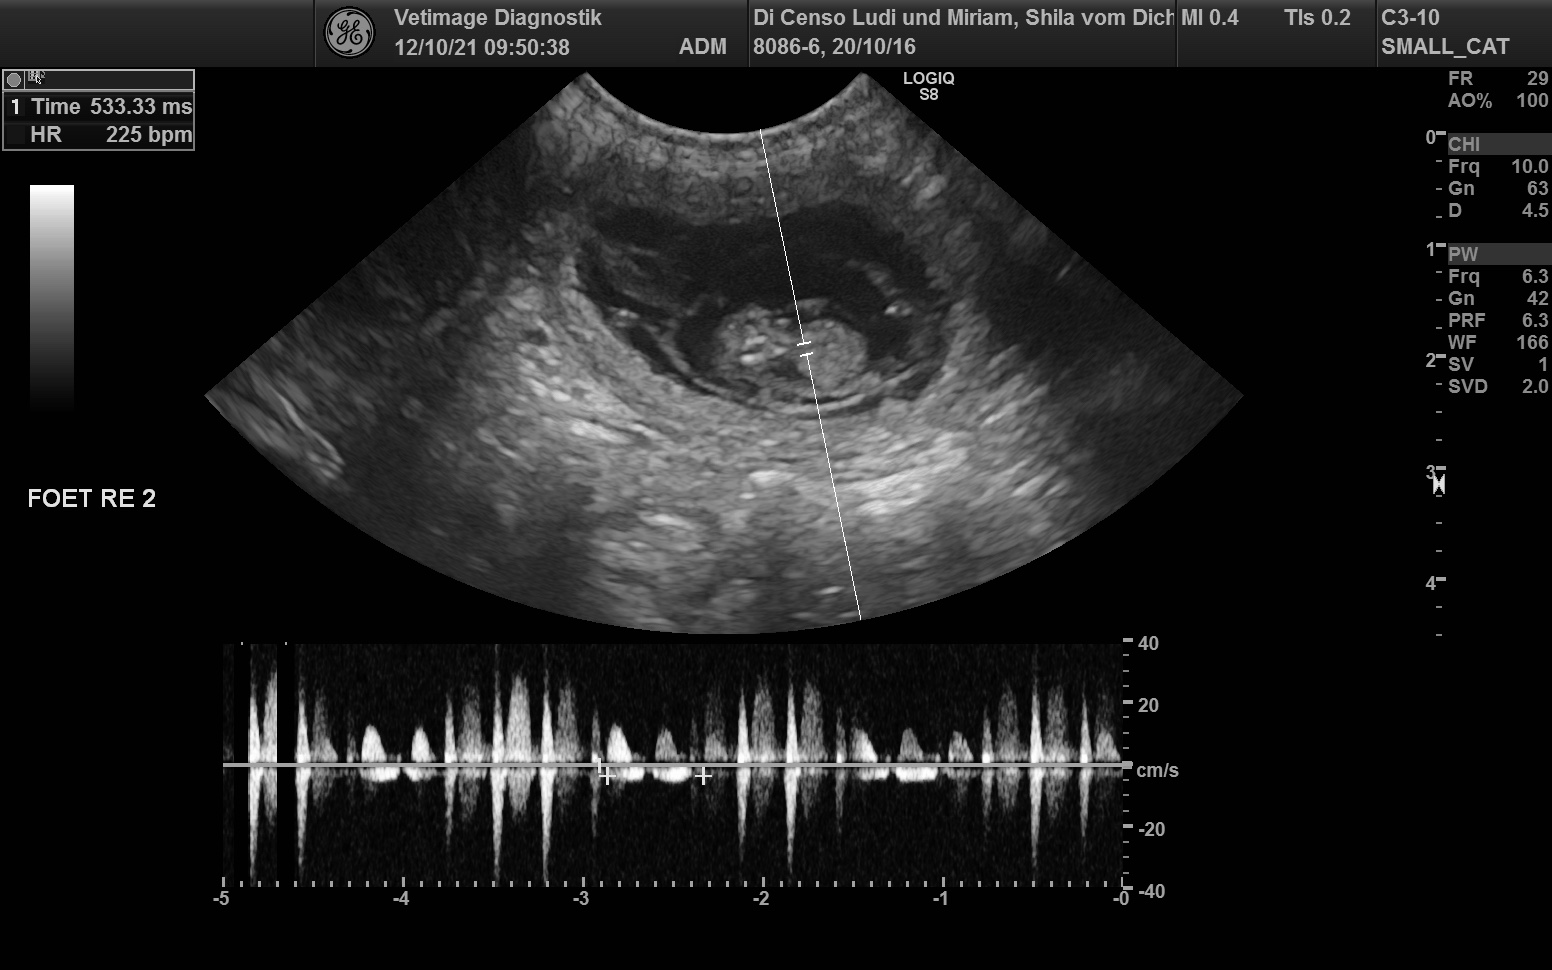

Wurfplanung mit Gwendy und Shila von LUMI’s Golden

Phinegean Coda of Golden Summerby wird Gwendy LUMI’s Golden und Shila vom Dichtereck decken!